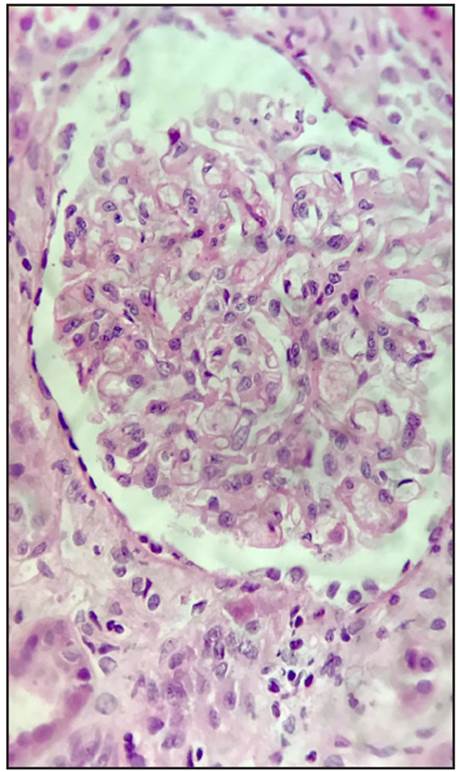

The biopsy report stated that 20 glomeruli were obtained; there was global sclerosis in five, with no mesangial or glomerular basement membrane abnormalities nor inflammatory changes in the glomeruli (Figures 1 and 2). There was 5% tubular atrophy, with no interstitial inflammation, myointimal thickening of the blood vessels and hyaline changes of the muscular wall with slight narrowing of the lumen (compatible with hypertensive nephrosclerosis). Immunofluorescence was negative for immune complex, complement (C3, C4, C1q), fibrin and light-chain immunoglobulin deposition. The main findings of electron microscopy or ultrastructural analysis were in the podocytes, with a loss of pedicels (their feet) in 70% of the capillary surface, and numerous zebra or lamellar bodies corresponding to lysosomal inclusions within them (Figures 3 and 4).